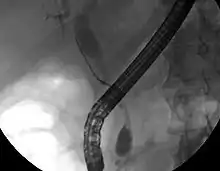

على الرغم من أنَّ التصوير البطني قد يكون كافيًا في تشخيص سرطانة الأقنية الصفراوية، إلا أنَّ التصوير المُباشر للأقنية الصفراوية يكون عادةً ضروريًا، ويعتبر تصوير البنكرياس والأقنية الصفراوية بالتنظير الباطني بالطريق الراجع (ERCP) من أكثر الإجراءات استعمالًا لهذا الغرض، وهو إجراءٌ تنظيري داخلي، يُجريه أخصائيُ الجهاز الهضمي أو جراحٌ خاصٌ مُتمَرس. على الرغم من أنَّ تصوير البنكرياس والأقنية الصفراوية بالتنظير الباطني بالطريق الراجع يُعتبر إجراءًا جراحيًا مُتوغل يتضمن أخطارًا مُصاحبة، إلا أنَّ مزاياهُ متعددة وتشمل القُدرة على الحصول خزعاتٍ، بالإضافة إلى وضع دعاماتٍ أو إجراء تدخلاتٍ أُخرى للتخفيف من انسداد الأقنية الصفراوية.[19]

يُمكن إجراءُ تنظيرٍ بالموجات فوق الصوتية في نفس وقت تصوير البنكرياس والأقنية الصفراوية بالتنظير الباطني بالطريق الراجع، مما قد يزيدُ من دقةِ الخزعة، وإعطاء معلوماتٍ حول مدى الانتشار إلى العقد اللمفاوية ومدى قابلية السرطانة للجراحة.[70] يُمكن استخدام تصوير الأقنية الصفراوية عبر الكبد عن طريق الجلد (PTC) بدلًا من تصوير البنكرياس والأقنية الصفراوية بالتنظير الباطني بالطريق الراجع. يُعتبر تصوير البنكرياس والأقنية الصفراوية بالرنين المغناطيسي (MRCP) البديل غير المُتوغل لتصوير البنكرياس والأقنية الصفراوية بالتنظير الباطني بالطريق الراجع.[71][72][73] اقترح البعض أنَّ تصوير البنكرياس والأقنية الصفراوية بالرنين المغناطيسي يجب أن يحل مَحل تصوير البنكرياس والأقنية الصفراوية بالتنظير الباطني بالطريق الراجع في تشخيص السرطانات الصفراوية؛ وذلك لأنهُ قد يحدد الورم بدقةٍ أكبر مع تجنب المخاطر المصاحبة لتصوير البنكرياس والأقنية الصفراوية بالتنظير الباطني بالطريق الراجع.[74][75][76]